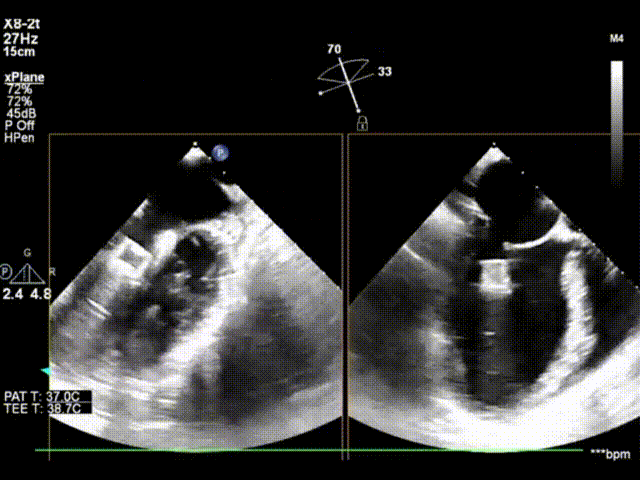

夹合后3D左房观,反流减少至轻微,跨瓣压差PGmax:6mmHg,PGmean:2mmHg

术前TEE检查发现该患者二尖瓣反流区域宽(18mm),缩流颈覆盖2个区,同时由于二尖瓣装置结构的改变,二尖瓣后叶拴系角度达70°,手术复杂性高、难度大,国际经验即使能行TEER也常需要多个夹子。国产自主原创的ValveClamp无论是夹合深度还是夹合范围都更大,能产生更强的瓣叶对合,适用于此类操作难度较大的病例。术前,瓣膜微创治疗团队详细讨论了手术方案,并结合ValveClamp结构与患者术前超声数据进行了手术预演,确保将风险降到最低。最后该患者使用二个夹子,反流基本消失,得到了良好的治疗效果。导管操作仅40分钟,夹合后跨瓣压差、瓣膜夹合量及瓣叶形态均呈良好状态。